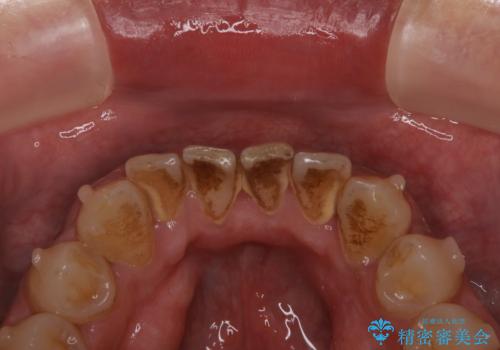

ホワイトニングは、歯を削ったり、傷つけたりすることなく歯の内部の象牙質まで浸透し、色素を分解して漂白することで、くすることができます。

- 知覚過敏が出ることがあります

- ホワイトバンドや白い斑点が出ることがあります

- クラウンやインレー等の補綴物には効果がありません